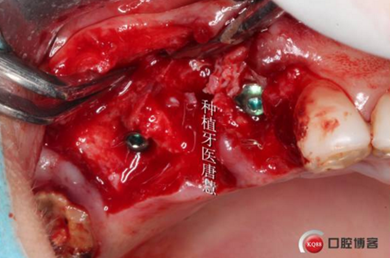

翻瓣,肉芽超多

15根尖區(qū)大塊肉芽腫

大量鹽水沖洗后

拔牙窩偏舌側(cè)備洞,13貼面對于植入方向判斷還是有一定迷惑的

植入植體

自體骨填充拔牙窩與植體間空隙

植入骨粉